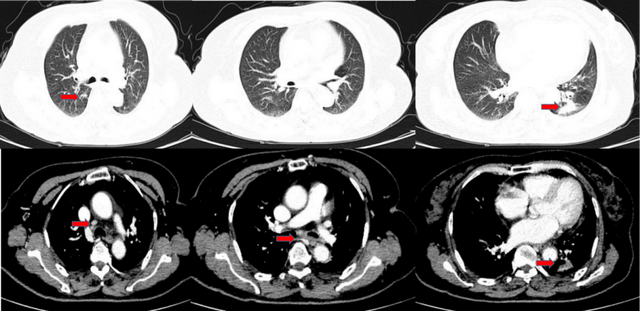

2019年4月11日胸部增强CT示左肺下叶后基底段占位性病变,考虑肿瘤性病变,肺癌伴阻塞性炎症;右肺上叶后段类结节,考虑肿瘤性病变,转移瘤;左肺门、纵隔多发淋巴结增大。胸11椎体右份骨质密度不均匀增高。

图1. 2019年4月11日胸部增强CT

图2. 2019年11月5日胸部CT复查结果(疗效评估为PR)

图3. 2020年11月19日胸部CT复查结果(疗效评估为PD)